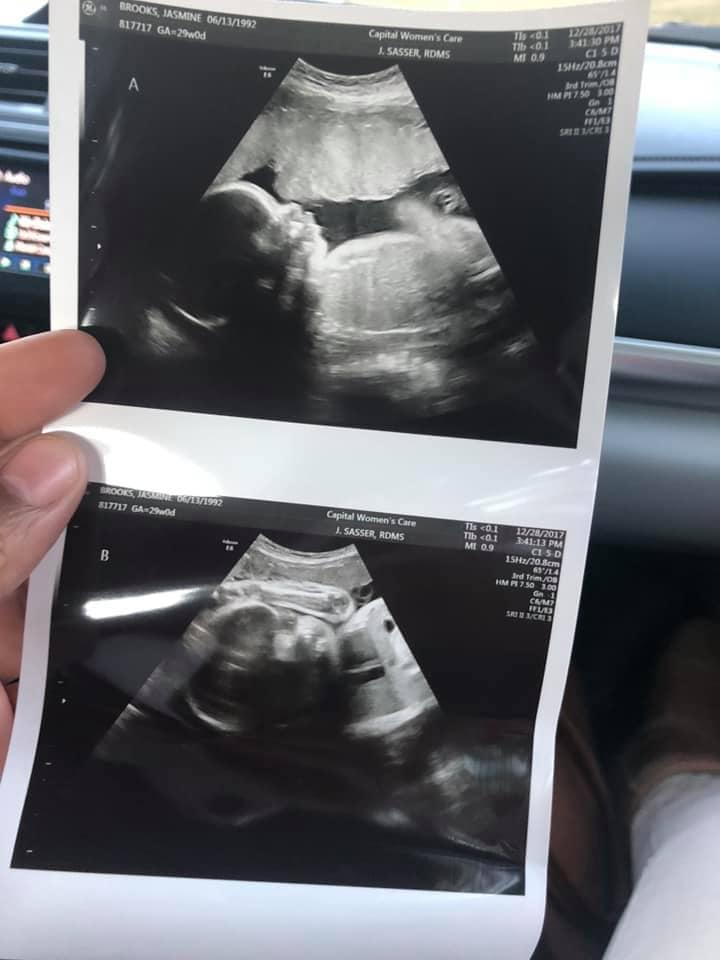

- Ultrasound photos at 29 weeks pregnant with twins

Ultrasound photos at 29 weeks pregnant with twins